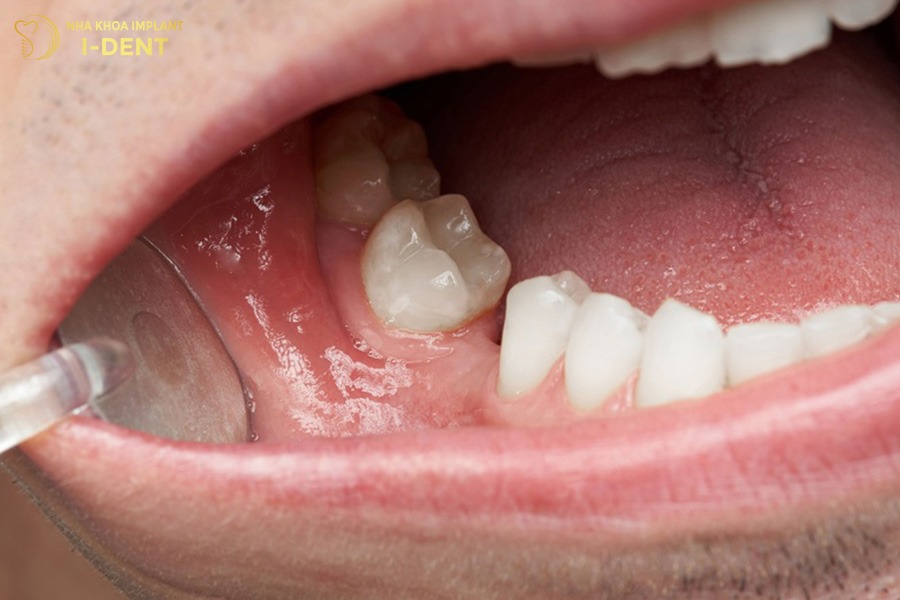

Khi một chiếc răng mất đi, các răng kế cận có xu hướng nghiêng về khoảng trống hoặc trồi lên, thụt xuống để lấp chỗ trống đó. Sự dịch chuyển này làm cho khớp cắn bị lệch, răng không còn ăn khớp chuẩn như ban đầu. Về lâu dài, tình trạng răng xô lệch khiến việc vệ sinh trở nên khó khăn hơn, tạo điều kiện cho mảng bám và vi khuẩn phát triển.

Khoảng trống mất răng khiến các răng kế cận nghiêng lệch, làm sai khớp cắn.